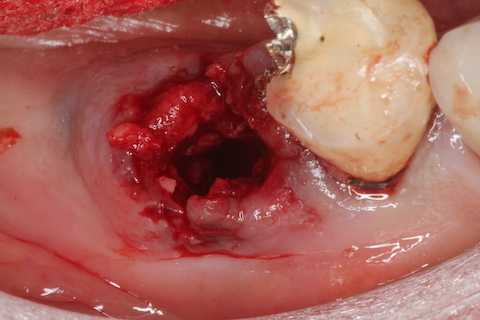

抜けた、、膿瘍がついてくる。疲れた

歯根端の膨らみはセメント質の肥厚だ。炎症が長年続くとこうなるということだが。

根尖が丸い。根尖口も閉じていない